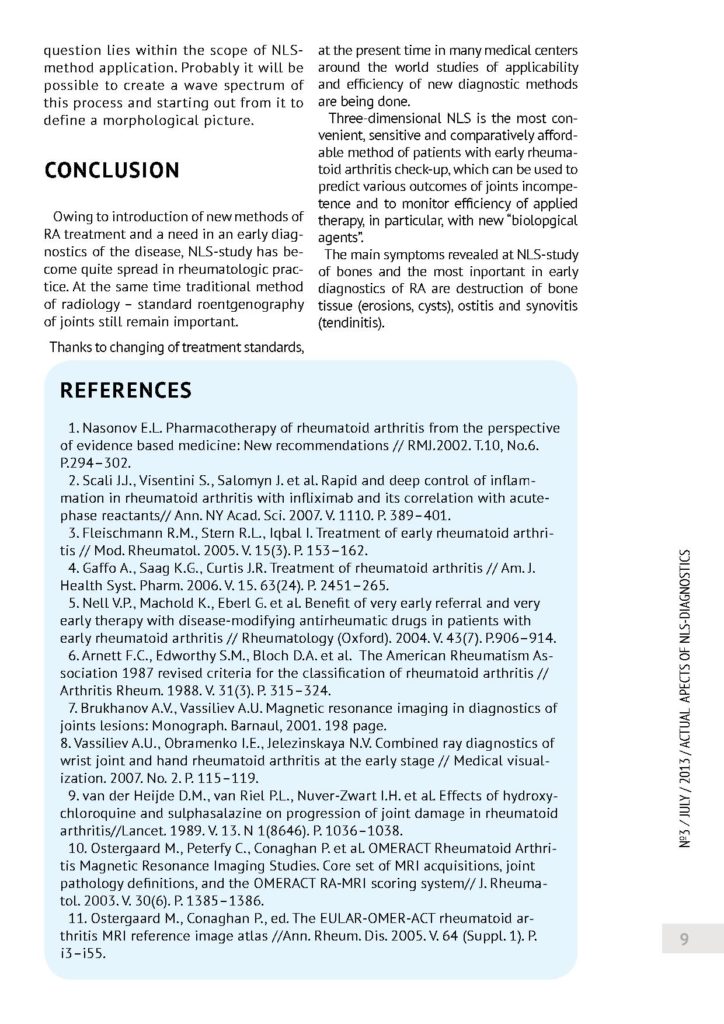

Trójwymiarowy NLS - w diagnostyce wczesnego reumatoidalnego zapalenia stawów